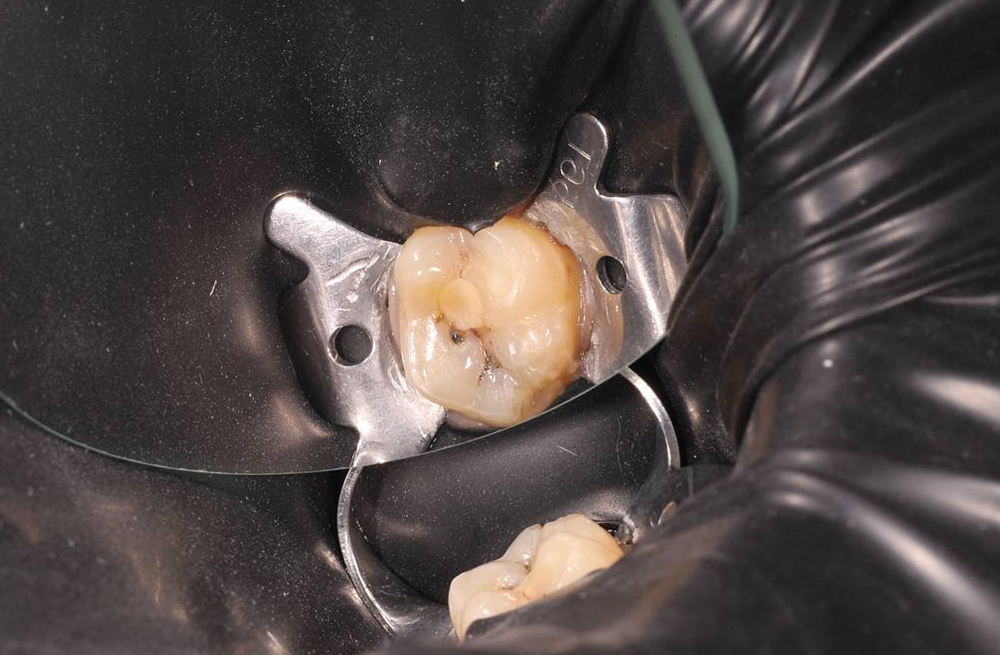

Устранение кариозного поражения зуба с применением коффердама и композитной реставрации